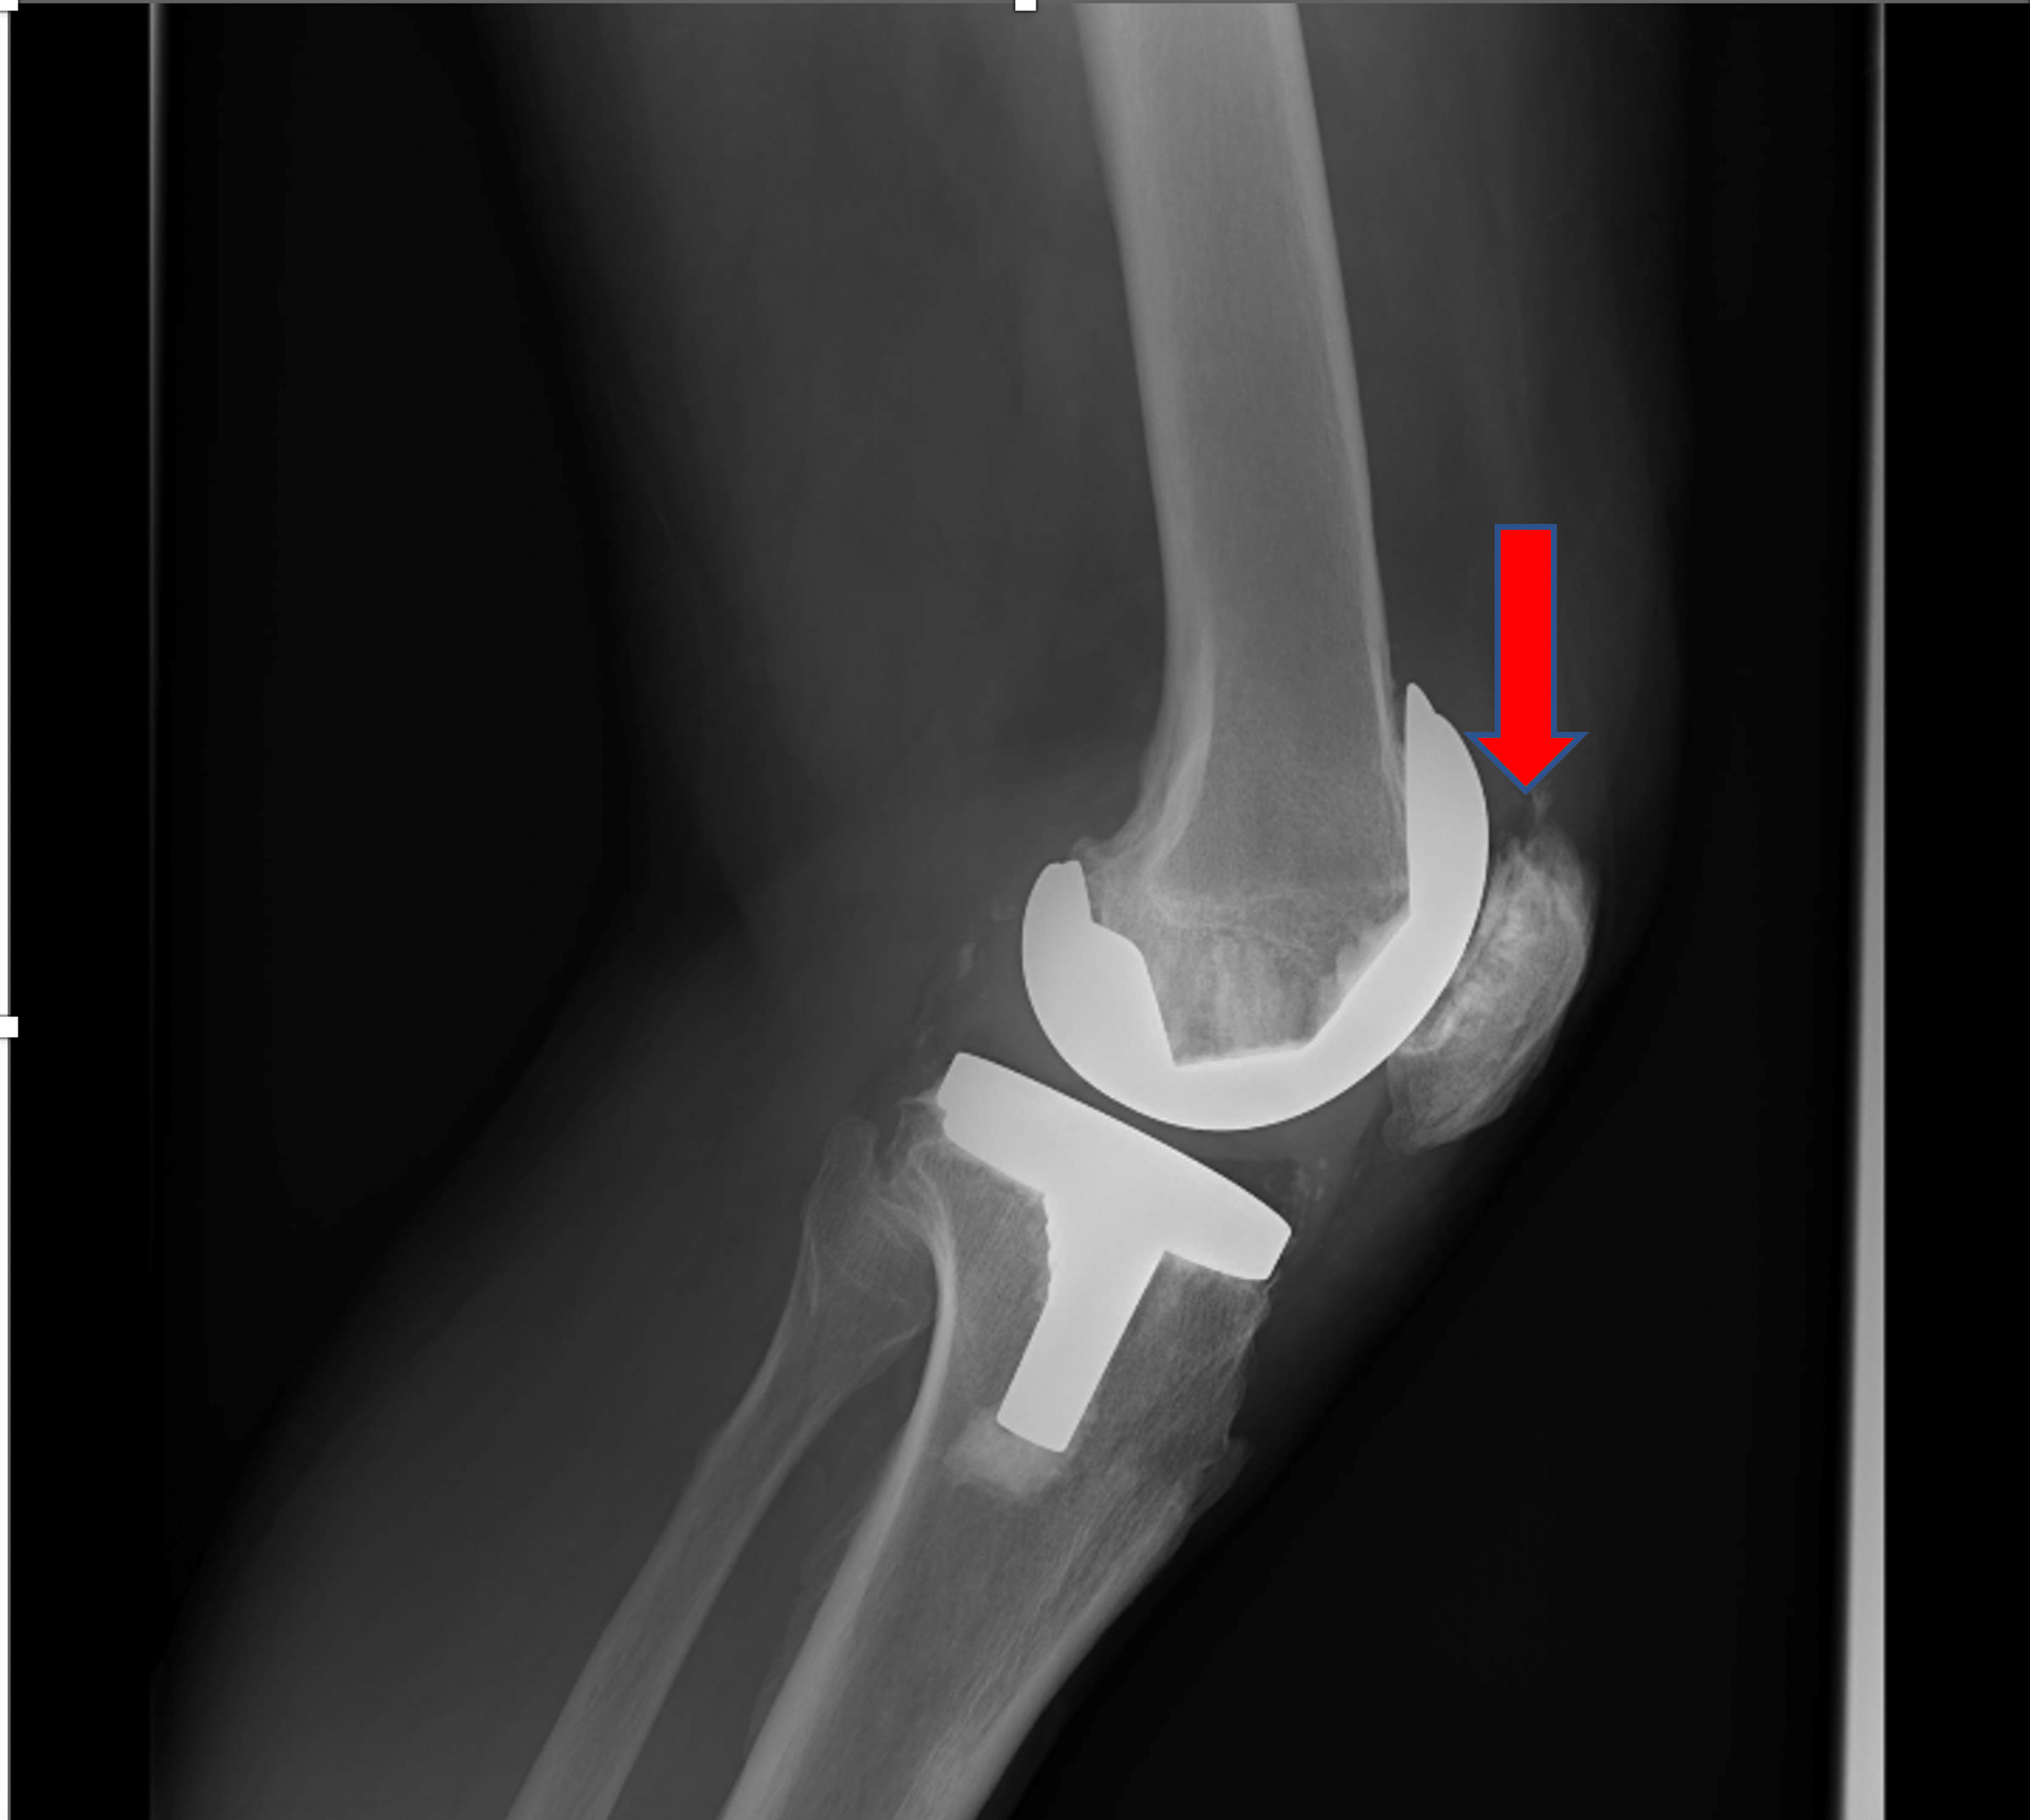

From www.cureus.com

A Rare Presentation of Patella Button Aseptic Loosening After a Total What Is Aseptic Loosening After Knee Replacement when revision surgery is needed in total knee arthroplasty (tka) the most frequent reasons are aseptic. Common causes of failure of knee arthroplasty include aseptic loosening,. aseptic loosening, characterized by the gradual separation of the implant from the bone without the. aseptic loosening remains one of the leading causes for failure of total knee arthroplasty (tka). We. What Is Aseptic Loosening After Knee Replacement.

A Rare Presentation of Patella Button Aseptic Loosening After a Total What Is Aseptic Loosening After Knee Replacement aseptic loosening remains one of the leading causes for failure of total knee arthroplasty (tka). During the first 7.3 years after reimplantation, 22% and. We sought to identify early. aseptic loosening, characterized by the gradual separation of the implant from the bone without the. aseptic loosening is the loosening of a prosthesis from bone in the absence. What Is Aseptic Loosening After Knee Replacement.

A Rare Presentation of Patella Button Aseptic Loosening After a Total What Is Aseptic Loosening After Knee Replacement During the first 7.3 years after reimplantation, 22% and. Common causes of failure of knee arthroplasty include aseptic loosening,. We sought to identify early. aseptic loosening remains one of the leading causes for failure of total knee arthroplasty (tka). aseptic loosening is the loosening of a prosthesis from bone in the absence of infection or trauma. aseptic. What Is Aseptic Loosening After Knee Replacement.